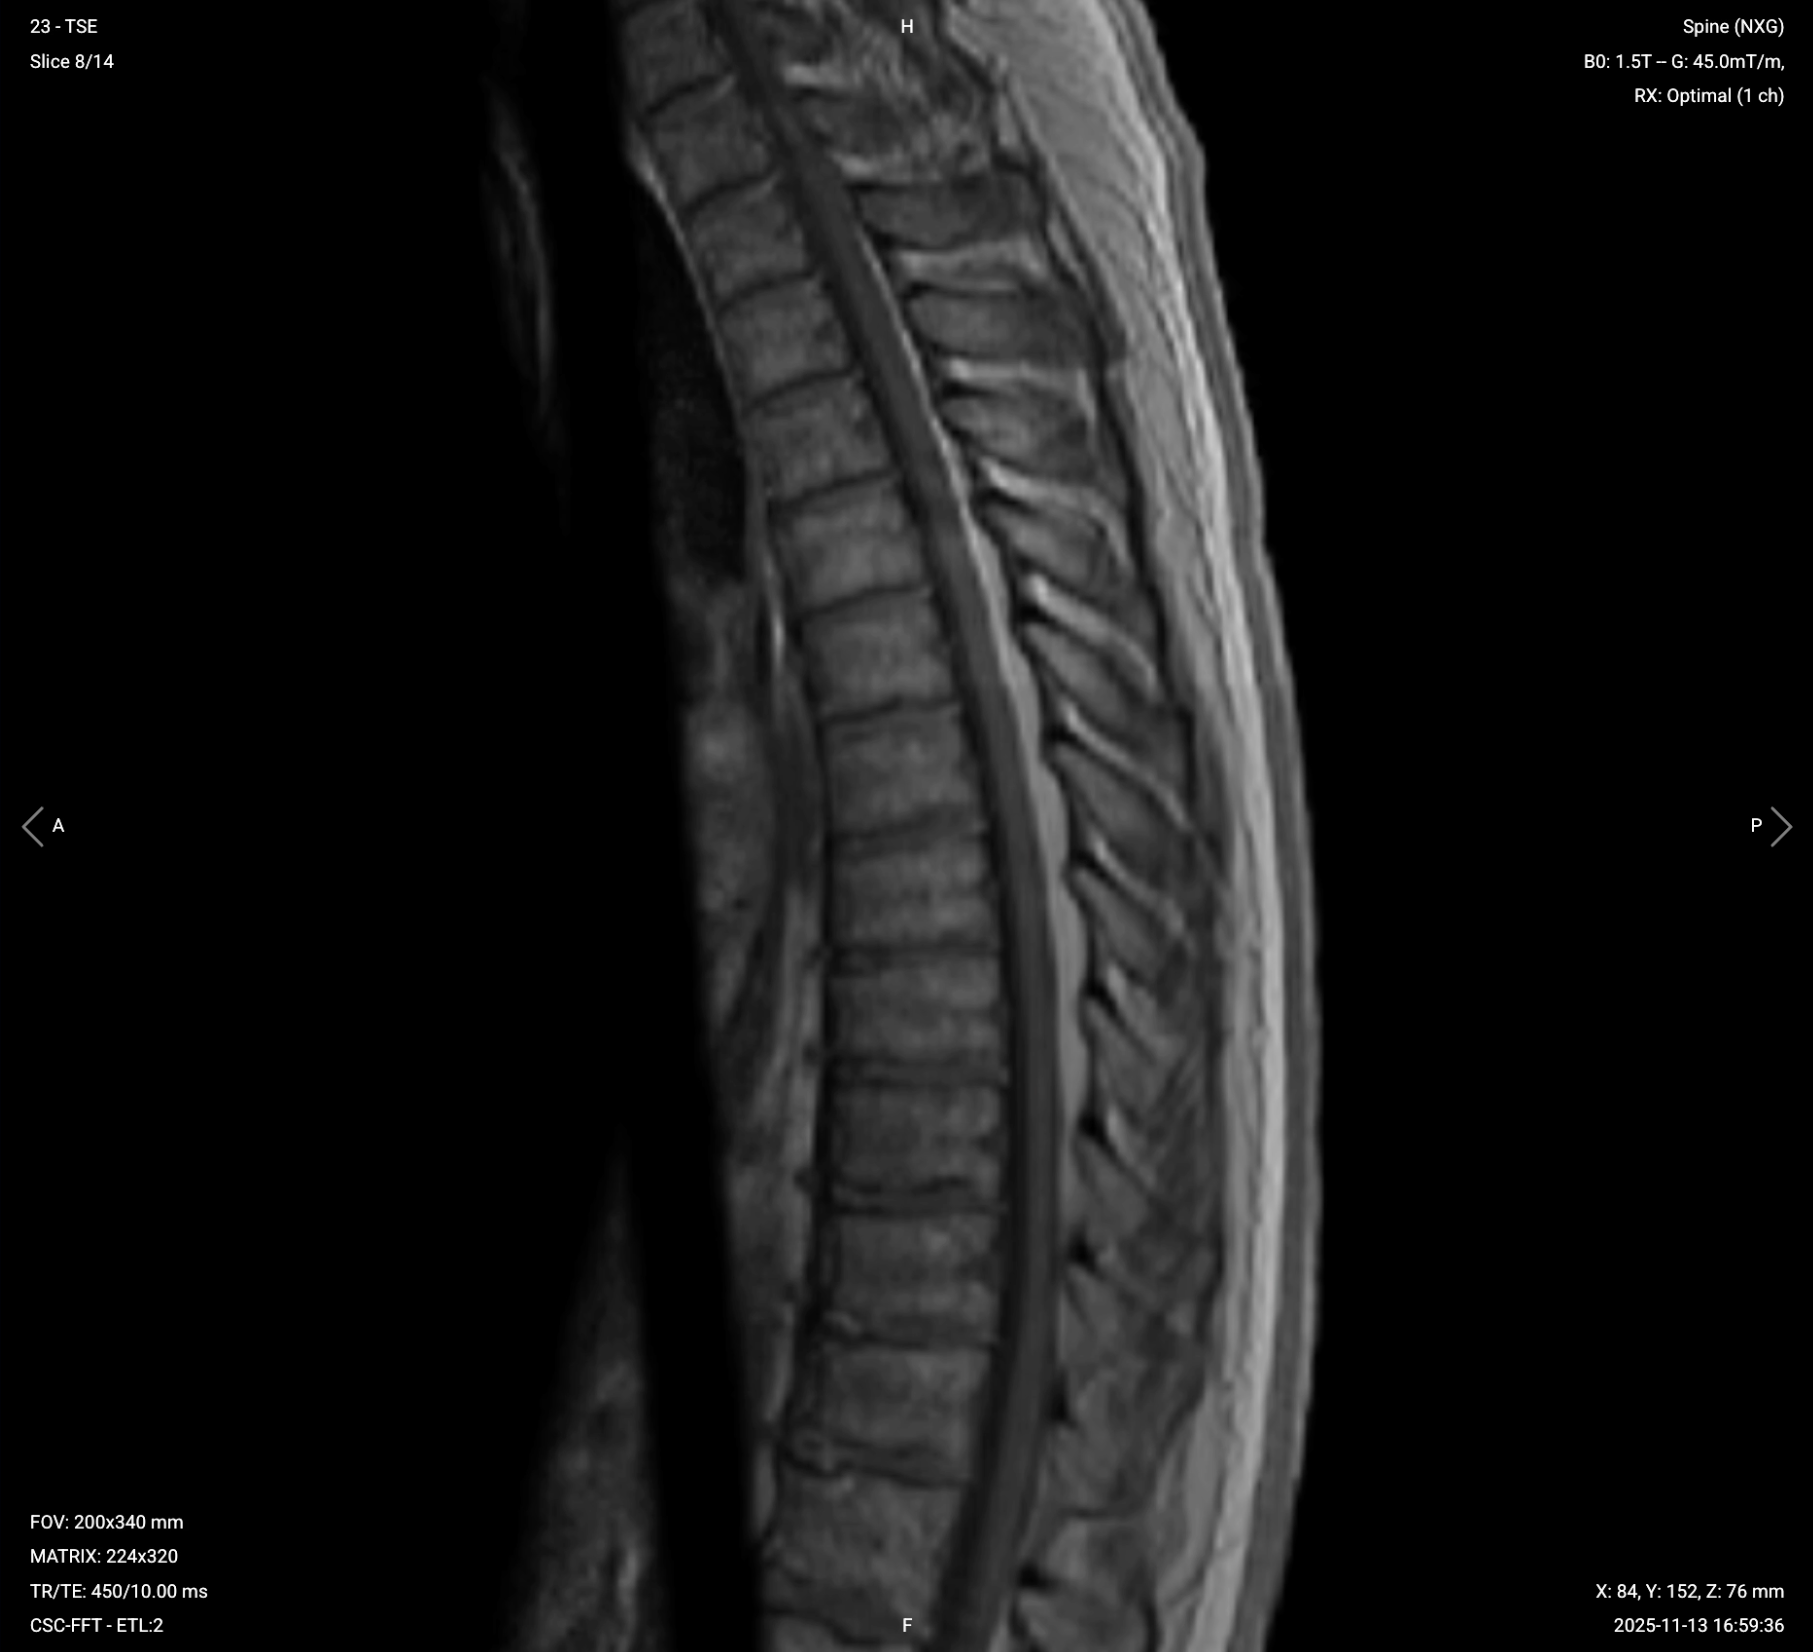

Parameters for Sagittal T1 TSE:

| Field-of-View (FOV) | 200 × 340 mm | Rectangular FOV optimized for the thoracic spine's vertical extent, covering superior-to-inferior while minimizing anterior-posterior to reduce scan time. |

| Matrix | 224 × 320 | Medium matrix size provides sufficient resolution while maintaining short scan time and high SNR. |

| Foldover Direction (Phase) | Foot-to-Head (FH) / Superior-to-Inferior | Aligns with cerebrospinal fluid flow to reduce flow artifacts. |

| Number of Slices | 14–18 | Covers the thoracic spine from right to left adequately. |

| Slice Thickness | 4 mm | Medium thickness provides good resolution without increasing scan time too much. |

| Slice Gap | 0.4 mm | 10% of slice thickness prevents crosstalk while maintaining continuity. |

| NEX / Averages | 1–2 | Provides adequate SNR while keeping scan time reasonable. |

| Turbo Factor / ETL | 2–3 | Low turbo factor minimizes T2-weighting and preserves pure T1 contrast. |

| Bandwidth | 50,000 Hz | Medium bandwidth balances SNR with chemical shift artifact reduction. Lower than typical values to improve SNR in the challenging thoracic region. |

| Fold-over Suppression | Yes | Prevents wrap-around artifacts. |

| Saturation Bands | Yes | Placed anterior to the spine to suppress cardiac, respiratory, and vascular motion artifacts. |

✅ Sagittal T1 TSE of Thoracic Spine – Correct Image Example:

Things to Look for in Sagittal T1: